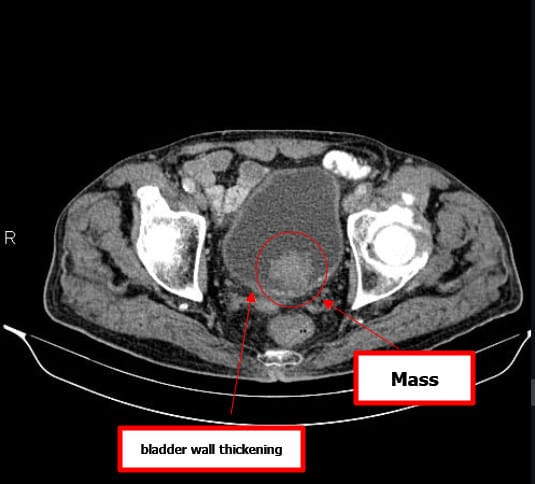

방광암 (Bladder Cancer)

[임상양상]

– 가장 특징적인 증상은 무통성 육안적 혈뇨입니다.

– 빈뇨, 배뇨통, 잔뇨감 같은 자극 증상이 동반될 수 있습니다.

– 진행 시 골반통, 수신증(요관 폐쇄), 체중 감소 등 전신 증상이 나타날 수 있습니다.

[진단]

– 소변검사: 혈뇨 확인.

– 소변세포검사: 암세포 확인 가능.

– 방광경검사(Cystoscopy): 진단의 gold standard, 직접 종양 확인 및 조직생검 가능.

– 영상검사(CT urography, MRI): 종양의 범위 및 전이 평가.

– 병리검사: 요로상피암(urothelial carcinoma), 편평상피암, 선암 등 조직학적 아형 구분.

방광암을 초기에 평가할 때 가장 흔히 시행

요로조영술 (Intravenous Urography, IVU)

조영제를 통해 요로계 구조를 간접적으로 시각화

CT

방광암의 병기 결정과 전이 평가에 가장 유용

MRI (Magnetic Resonance Imaging)

연부조직 대비가 뛰어나 방광 침윤 깊이를 정밀하게 파악